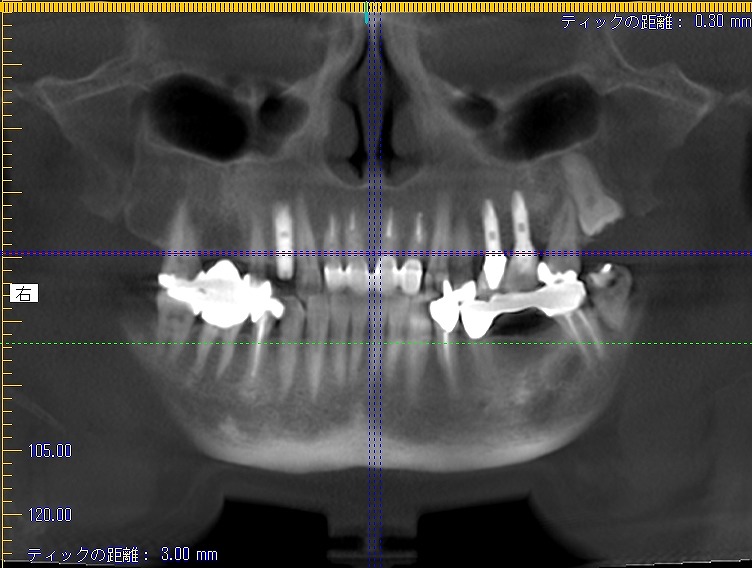

術後のCTになります

頬側の骨幅も維持できていました